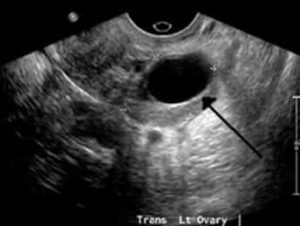

کیست تخمدان

درد ناگهانی یا مبهم در سمت چپ شکم پایینپیچخوردگی تخمدان (تورشن)